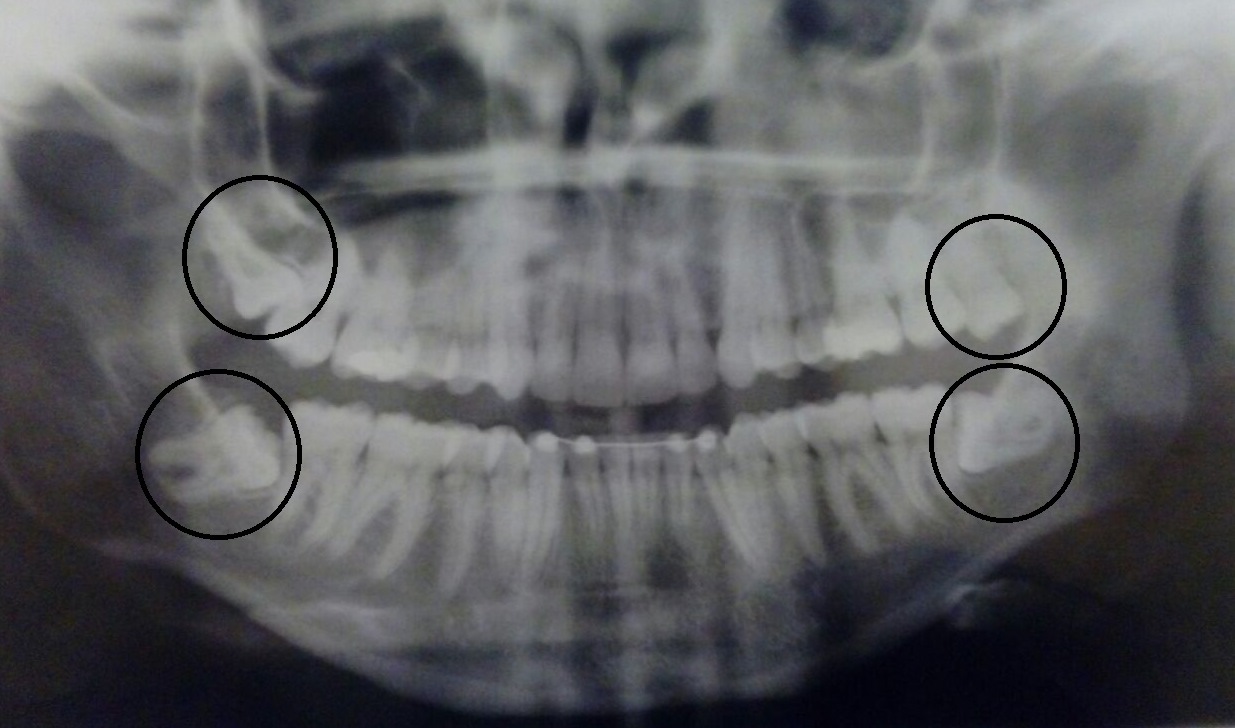

Anos e anos depois, eu aqui na Alemanha comecei a ter as mesmas dores (e elas sempre mais fortes). Fui consultar um dentista novo e ao invés ele dizer algo a respeito dos meus dentes, me enviou para uma clínica de Kieferorthopädie (Ortodontia). Lá a médica consultou, escutou os barulhos altos que saíam do meu maxilar e me mandou fazer um Raio-X dos meus dentes. Observe na imagem:

Esse foi o meu resultado… nenhum “dente do juízo” estava no lugar certo. Toda a pressão que eles estariam gerando em cima dos outros dentes poderia ser o causador das minhas dores. Minha dentista na hora escreveu uma carta para meu dentista dizendo que em questão de 6 meses eles deveriam de estar fora da minha boca.